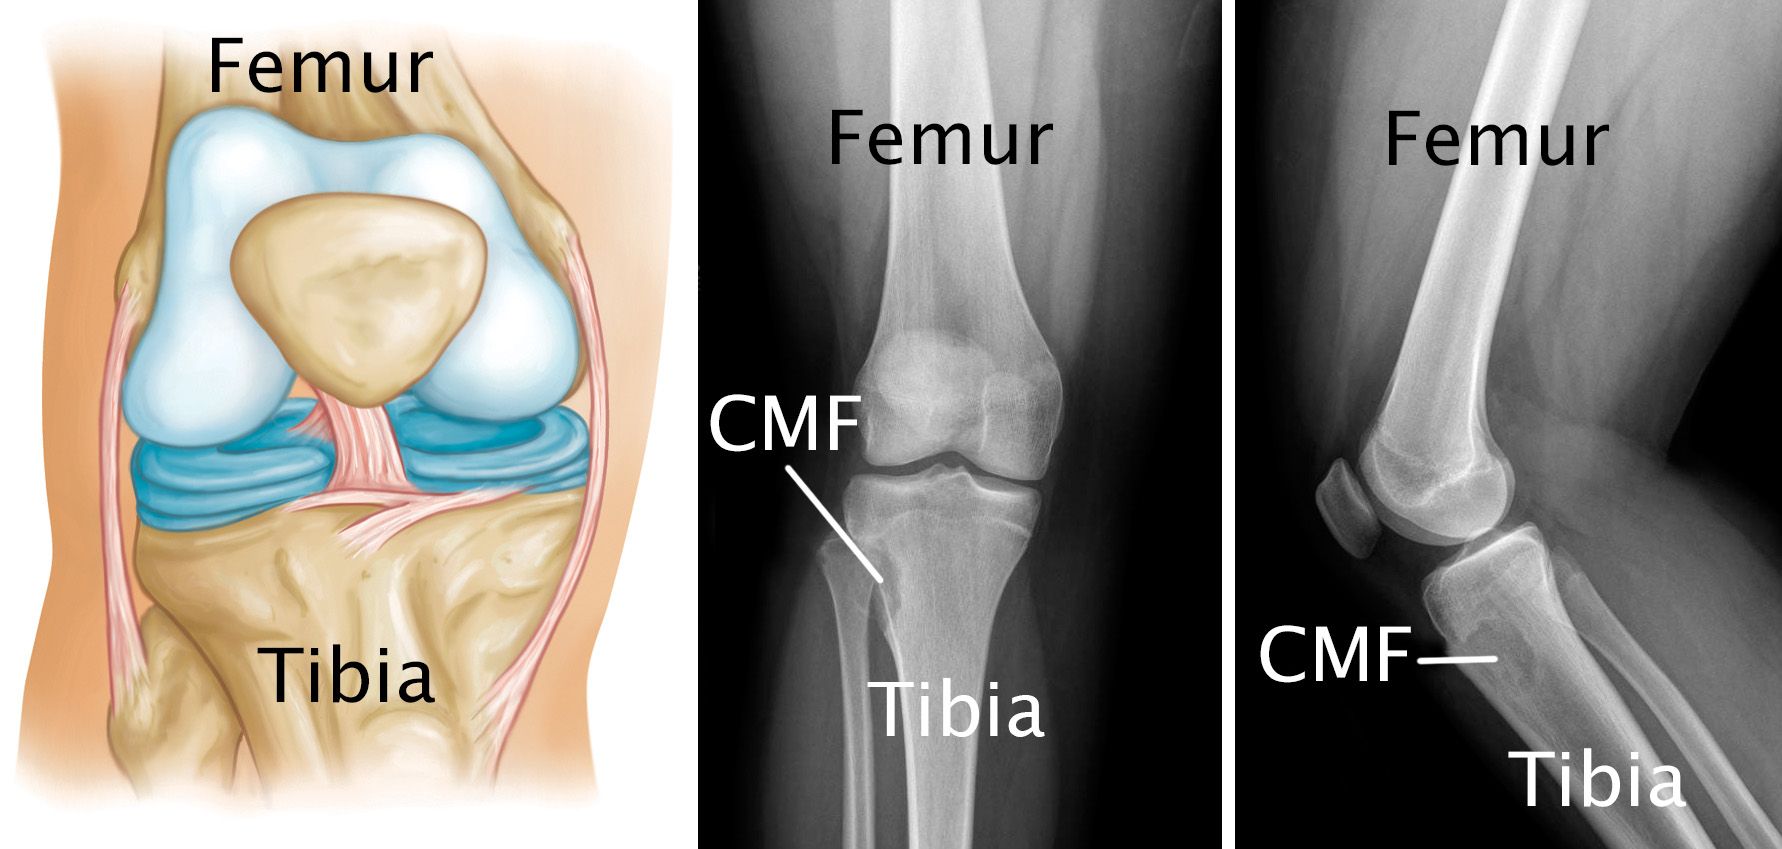

x-rays of a chondromyxoid fibroma

(Left) Normal knee anatomy. (Center) This X-ray shows a CMF tumor in the end of the tibia near the knee. (Right) This X-ray provides a side view of the same CMF tumor.

X-rays. X-rays provide clear pictures of bone and are very helpful in diagnosing CMF. Most chondromyxoid fibromas are small (1 to 4 cm), round- or oval-shaped tumors. In X-rays, they are often surrounded by a white (sclerotic) rim of bone.

In many cases, the tumor will destroy portions of the bone and aggressively grow, pushing into the surrounding soft tissues. This is why some patients can feel a bump through the skin.